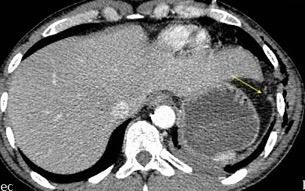

Recibe una puñalada en costado izquierdo

La laceración tiende a ocurrir en la unión

músculotendinosa . (64-90% en el lado izquierdo)

Diafragma “colgante” (“dangling sign”)

(“Dangling sign”)

TC. Mejor con multicorte. (reconstrucciones).

Asociación: Aire en pared.

Fracturas costal .Rotura esplénica. Neumoperitoneo.

Diafragma discontinúo Herniación de la grasa omental

Desser TS et al.The dangling diaphragm sign: sensitivity and comparison with existing CT signs of blunt traumatic diaphragmatic rupture. Emerg Radiol 2010